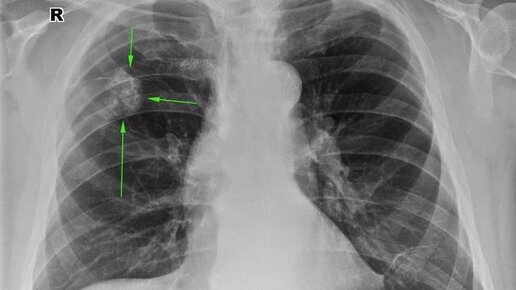

Какие очаги врачи могут выявить в лёгких

Довольно часто можно услышать врачебную фразу про выявление у пациента «очага или очагов в лёгких». Что же представляют собой подобные очаги и когда они возникают разберем в данной статье.

Очаги в лёгких...